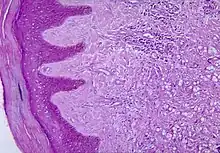

Diagnosis

Diagnosis of Lobo's disease is made by taking a sample of the infected skin (skin biopsy) and examining it under the microscope.[4] Lacazia loboi is characterized by "lemon-shaped" fungi, a "sieve-like" appearance due to unstained fungi, and long chains of spherical cells interconnected by tubules.[4]

The cells appear to be yeast-like with a diameter of 5 to 12 μm. Attempts to culture L. loboi have so far been unsuccessful.